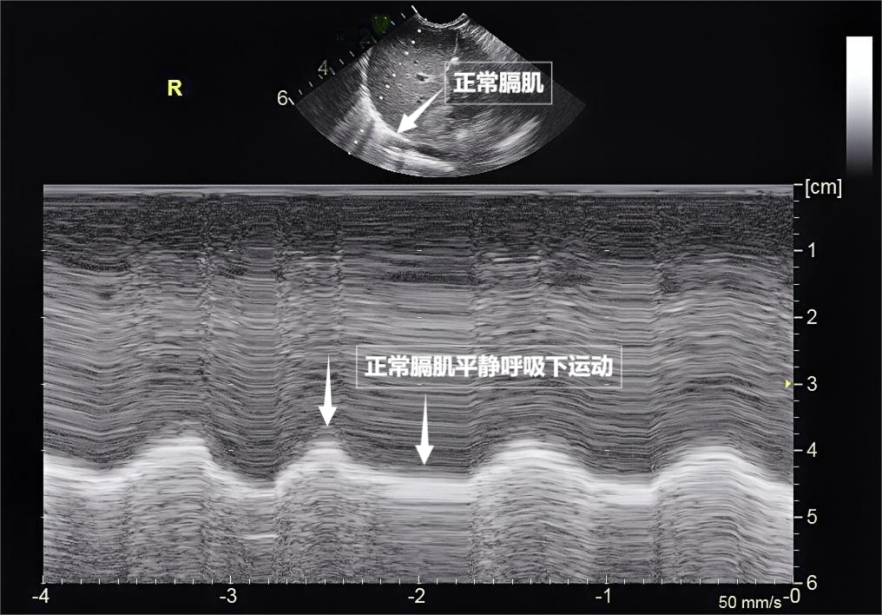

呼吸看似简单,实则是多组肌肉精密配合的“团体操”。肺部超声不仅能观察肺的形态,更能通过实时动态影像,“捕捉”这些呼吸肌的活动状态,为评估呼吸功能提供独特视角。膈肌是呼吸肌的“总指挥”,位于胸腔与腹腔之间。平静呼吸时,膈肌收缩下沉,胸腔容积扩大,空气自然吸入;舒张时,膈肌回升,肺部弹性回缩完成呼气。超声下可见膈肌呈光滑弧形,随呼吸规律上下移动(见下图)。肋间外肌则是“肋间隙的升降机”,收缩时上提肋骨,扩大胸腔前后径,辅助吸气。这对“黄金搭档”承担了日常呼吸70%以上的工作量,是维持呼吸的“主力军”。

▲图为正常膈肌超声表现